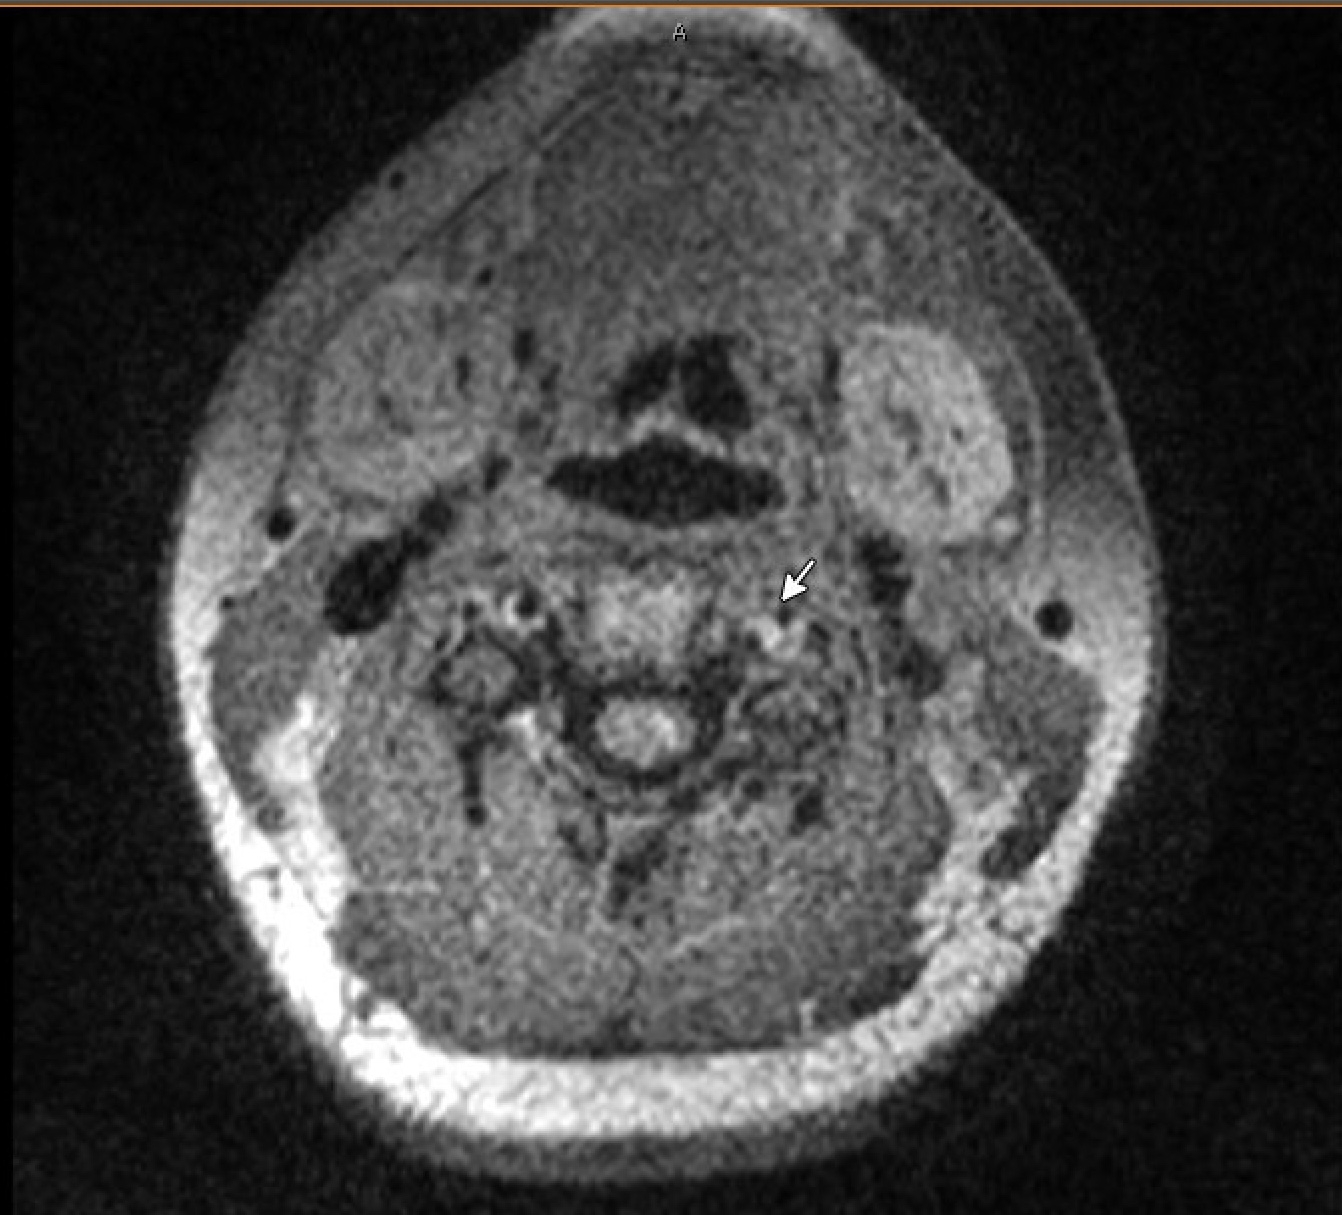

A total of 47 patients were identified with intracranial abnormalities initially picked on CTA. Of the total cases, 20 were initially suspected of CAD based on CTA, but only 13 were confirmed with dissections on VW-MRI. Amongst the seven cases which did not have a CAD on VW-MRI - two of them turned out to be artifactual, one of them was Fibromuscular Dysplasia (FMD), three showed atherosclerotic plaque and one was suggestive of a vasculitic process. In two cases, intracranial dissections were easily picked on VW-MRI, and in one case mural hematoma and in other two cases intraluminal thrombus were seen easily on VW-MRI, which were primarily missed on CTA.

Upon reviewing the patients during this period, it is evident that VW-MRI not only aids in localizing acute ischemic strokes but also plays a critical role in identifying CAD. Additionally, intracranial artery dissections, intramural hematomas, intraluminal thromboses and pseudoaneurysms had a better visualization on VW-MRI than on conventional CTA. VW-MRI adds value to the diagnosis of CAD, which can be beneficial in determining etiology of acute ischemic strokes for cases which have some degree of uncertainty and eventually may prove to be helpful in their long-term management.